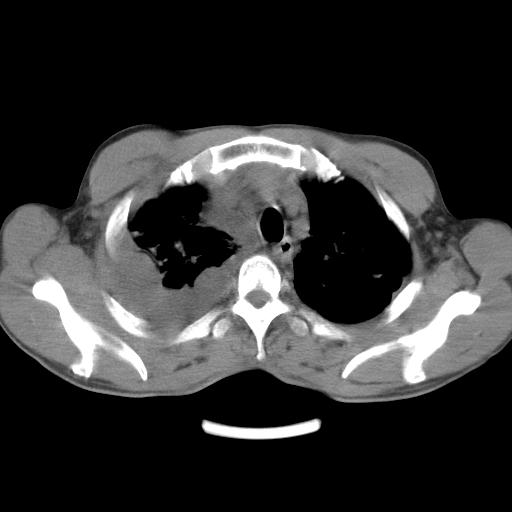

男性,44岁,结核病史多年。现胸闷气短,咳嗽,偶咳血。

1)两肺继发性肺结核伴空洞形成,左肺多发性结核球。2)右侧大量胸腔积液伴右肺部分膨胀不全。3)纵隔淋巴结肿大。

支持1)两肺继发性肺结核伴空洞形成。2)右侧大量胸腔积液伴右肺部分膨胀不全。3)纵隔淋巴结肿大。

吉大一院胸水抽检结果:结核性胸水